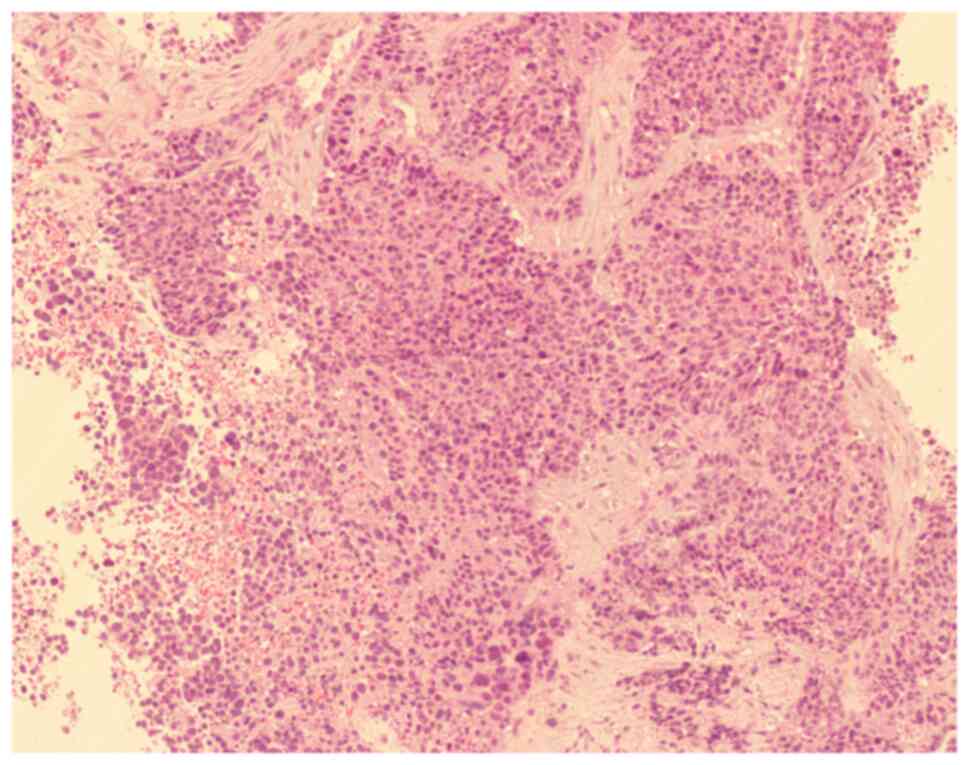

Multiple synchronous primary malignant neoplasms: A case report and literature review

Multiple primary malignant neoplasms (MPMN) are defined as two or more primary malignancies diagnosed in an individual. There is no association between these cancers, which can be classified into synchronous and heterochronous cancers depending on the time of diagnosis. The present study presented a rare case of bilateral breast, endometrial, cervical and ovarian cancers. Through thorough physical examination, pathology and immunohistochemistry, it could be determined that bilateral breast, endometrial and cervical cancers were primary malignant tumors and that ovarian cancer cannot be excluded as a result of metastasis. the present study also summarized the definitions, risk factors, prevalence characteristics, diagnostic ideas and treatment options for MPMN by reviewing the literature.